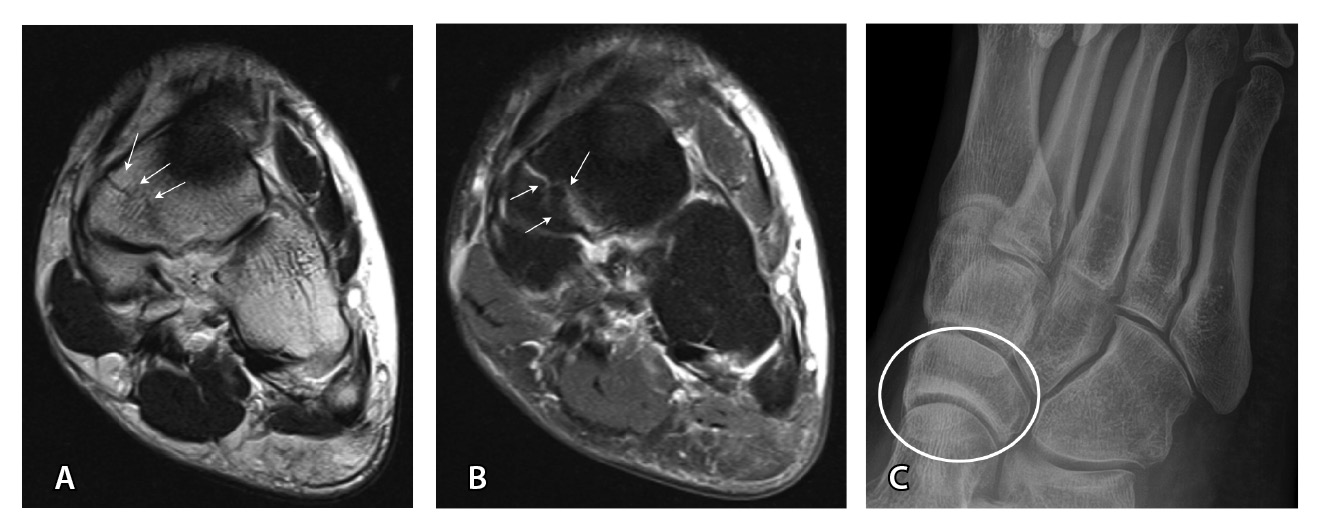

МРТ – наиболее подходящий метод визуализации остеохондрального повреждения купола таранной кости с чувствительностью и специфичностью 96% [52]. В исследованиях M. Haubro и соавт. [53], M. P. Wilson и соавт. [28] МРТ квалифицирована как золотой стандарт диагностики скрытых переломов по сравнению с КТ и рентгенографией. Протокол, состоящий из корональных T1-взвешенных изображений и STIR, обладает 100% чувствительностью в выявлении рентгеннегативных переломов (рис. 3) [28].

МРТ – первоначальный метод диагностики при подозрении на стрессовые переломы, так как ранним признаком таких переломов служит отек костного мозга пораженной кости, ярко выделяющийся среди остальных неизмененных костей. Отсутствие визуализации костного мозга затрудняет диагностику такого рода повреждений при рентгенографии и КТ (рис. 4). Чувствительность МРТ в выявлении стресс-переломов достигает 99% (95–100%), а специфичность – 97% (88–100%). Несмотря на то что исторически сцинтиграфия была основным методом обнаружения стресс-переломов с почти 100% чувствительностью, в настоящее время выполнение радионуклидного метода не рекомендуется из-за его низкой специфичности и высокой дозы ионизирующего излучения [54].